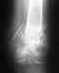

Замедленное сращение оттого, что кровоснабжение фрагментов нарушено травмой, возможно, еще и операцией. Ваши "нехотения" на него не влияют. Надо хотя бы динамизировать (отпереть) гвоздь, убрав вверху или внизу статический винт. Если после этого месяца за 3 (при продолжении ходьбы с полной нагрузкой) явных сдвигов к лучшему не будет - лучше заменить гвоздь.